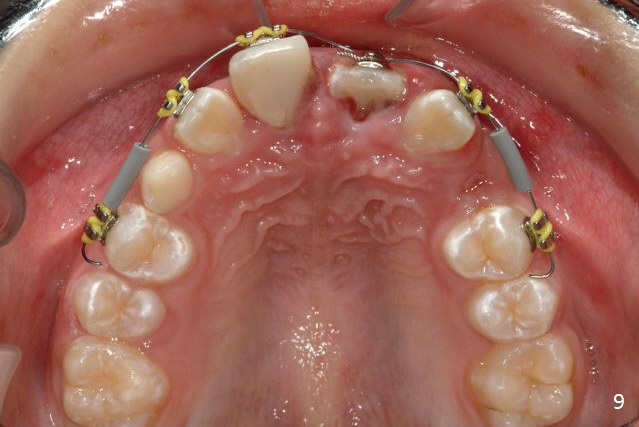

A 10-year-old boy has had Class II Division II malocclusion (Fig.1 impression taken 1 year earlier). He is brought to clinic the 2nd day after a bike accident. The tooth #8 fractures (Fig.2-4) with mesial pulpal horn exposure (Fig.3 *, while #9 intrudes. After debridement of the affected teeth (Fig.5), the exposed pulpal tissue is resected (partial pulpotomy to keep the tooth vital to finish root and apex development) and the pulpal horn is filled by MTA at #8 (Fig.6 *). The tooth #8 is restored with composite (Fig.7 C). Forceps fail to extrude the tooth #9. His parents are reluctant to accept orthodontic extrusion, which is accomplished by Dr. Shaughnessy 2 days later (Fig.8,9). The patient will leave for China in 2 days and will return in a month.